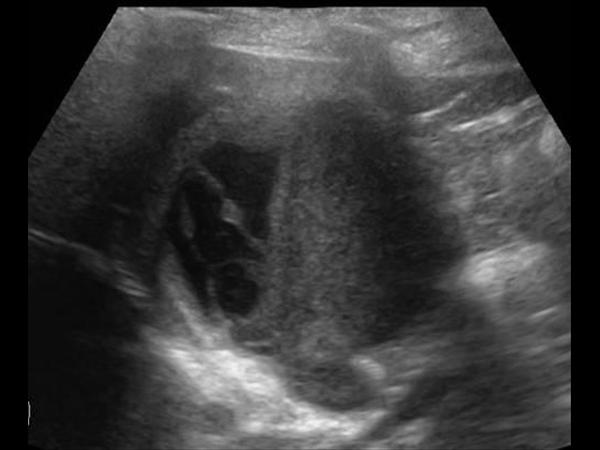

Chảy máu túi mật

Chảy máu túi mật - Ảnh 4

» Thông tin: Nữ giới – 81 tuổi.

» Lâm sàng: Đau mạn sườn phải / Sau thủ thuật ERCP.